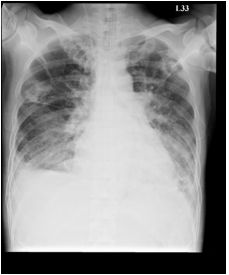

2. A 27-year-old woman had productive cough for one month.